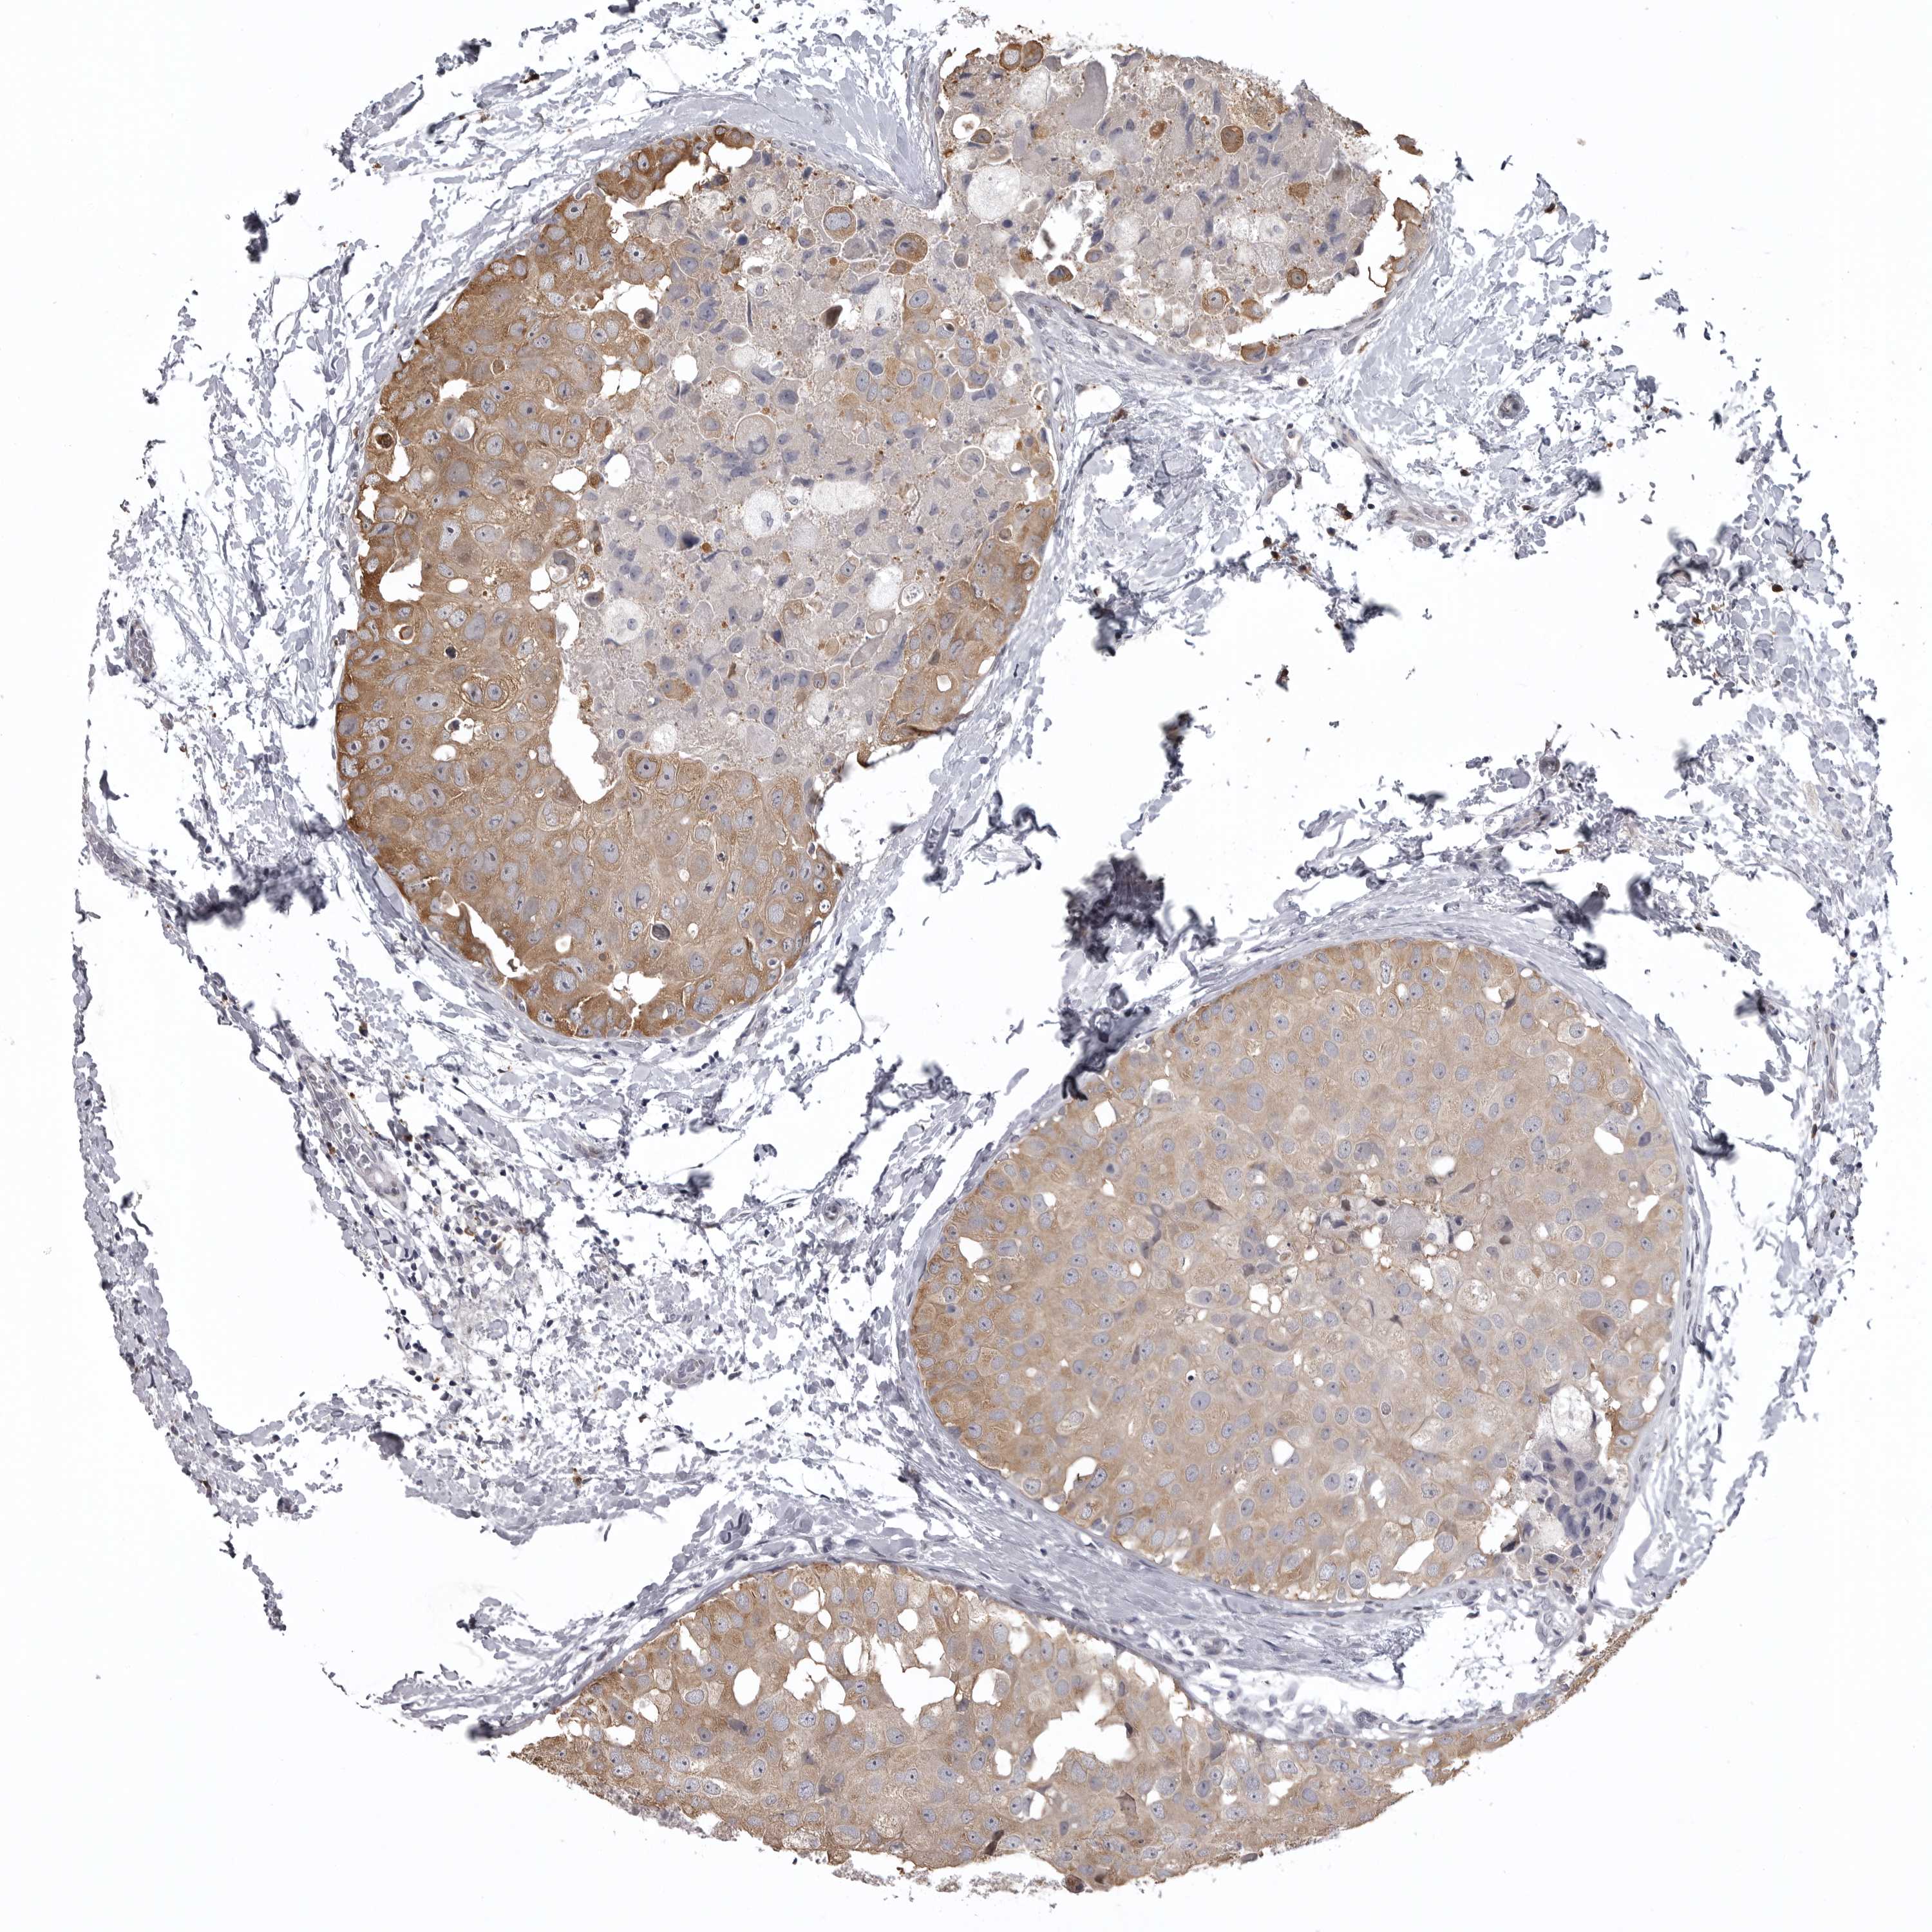

BRCA TCGA BRCA VALIDATION PROTEIN EXPRESSION

ANTIBODIES

AND

VALIDATION